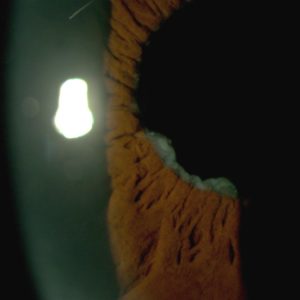

Figure 2:

Amplified slit-lamp photography showing heterogeneity in the morphological arrangement of iris varices, from flat radial sinuous veins to multi-saccular circumferential tufts.